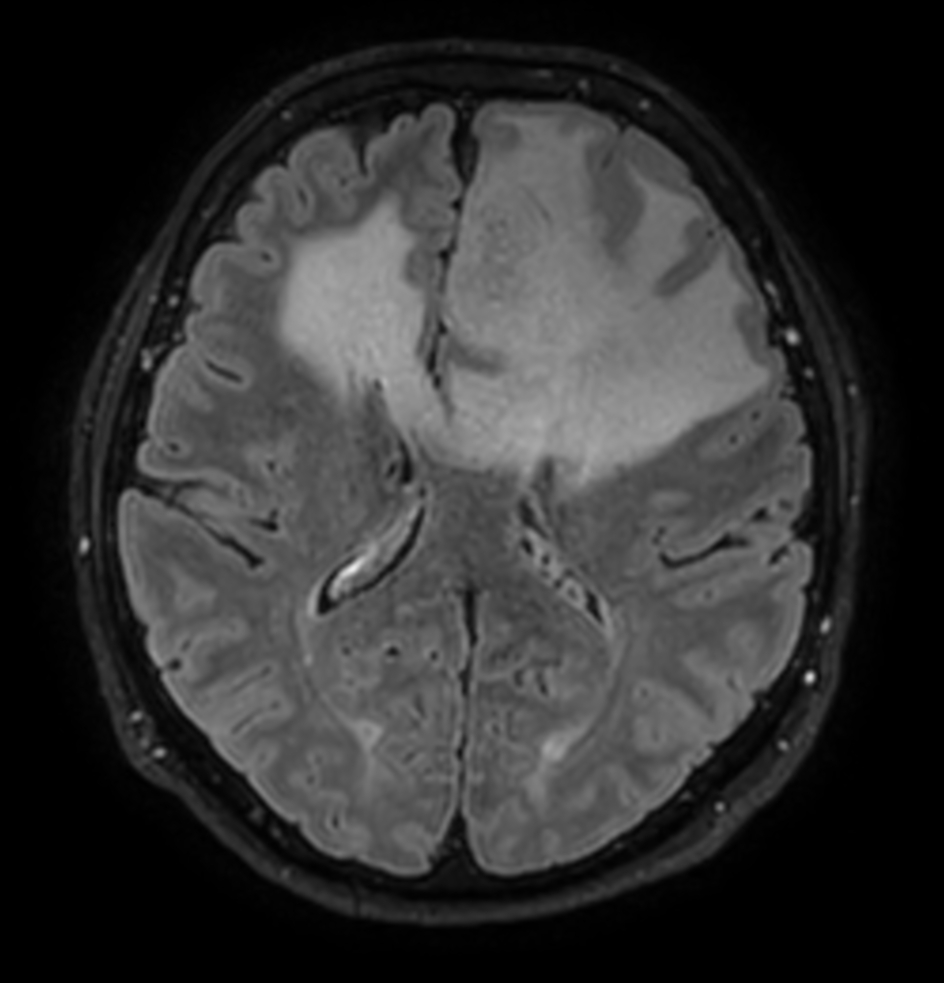

3D VIEW - T2w FLAIR